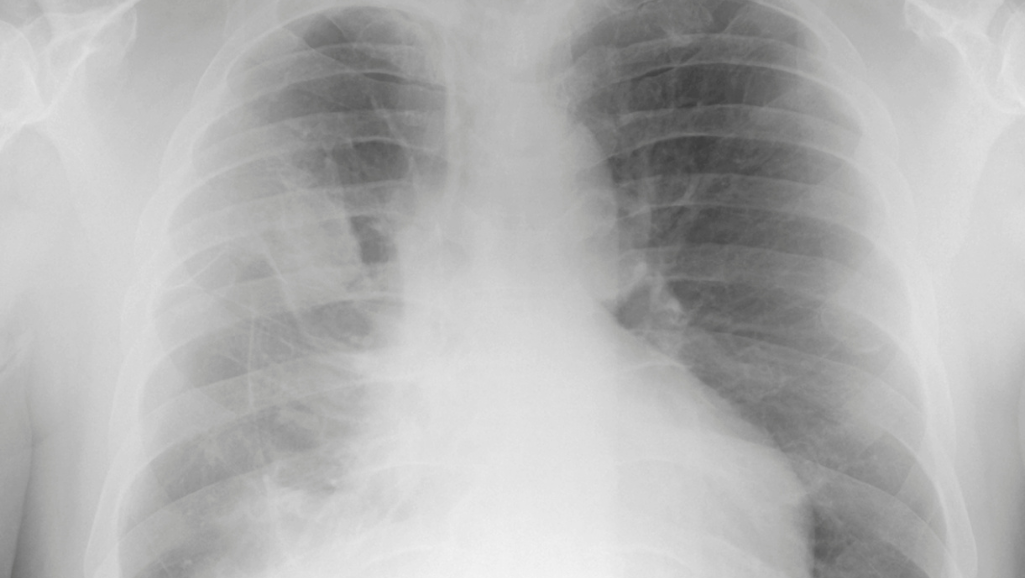

• Radiografia del torace: Questo è uno dei primi esami effettuati, utile per rilevare anomalie nei polmoni o nella pleura.

• Tomografia Computerizzata (TC): La TC è più dettagliata della radiografia del torace e può rivelare la presenza e l'estensione del tumore, nonché la diffusione ad altri organi.